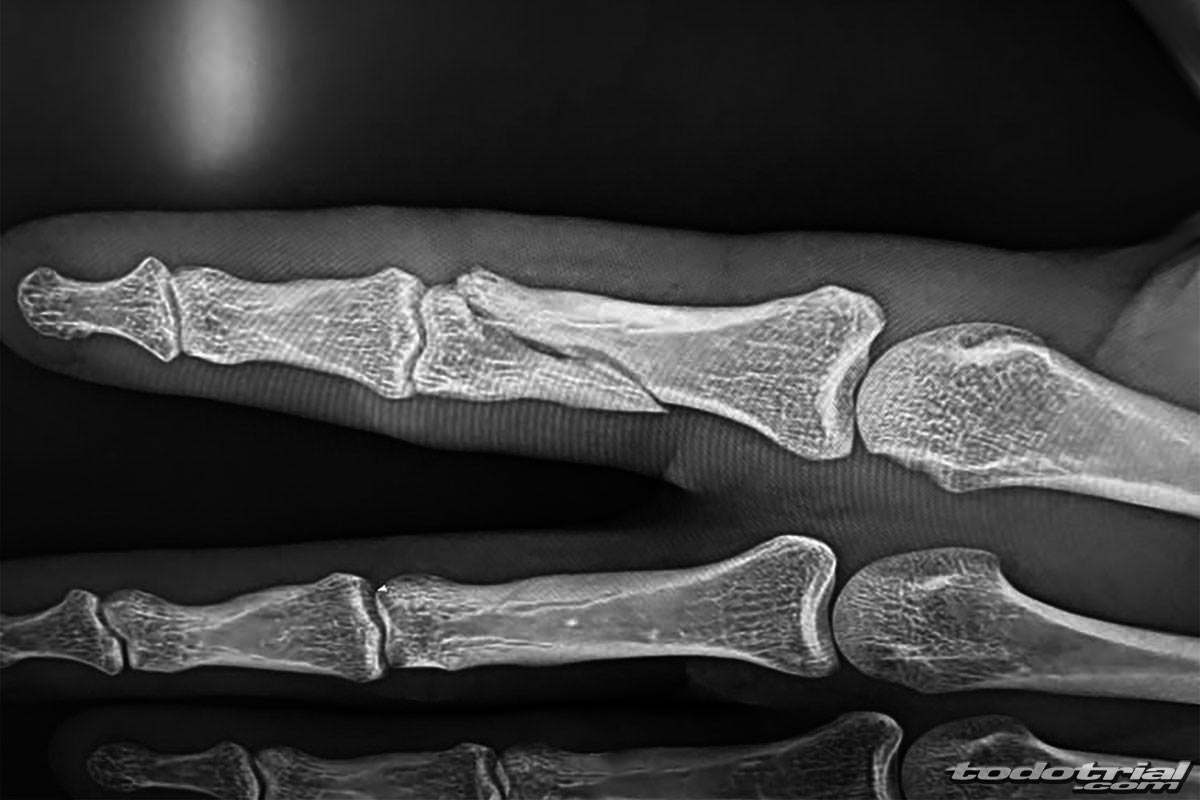

El propio piloto anunció así la lesión a través de sus redes sociales, acompañando el mensaje con una radiografía: «Malas noticias!! Una fuerte caída en el GP de USA nos va a dejar parados un tiempo!! Fractura en el índice de la mano izquierda. El jueves pasaremos por quirófano para estar de vuelta lo antes posible.»

Este tipo de fractura suele requerir la colocación de una placa con tornillos, lo que podría acelerar su recuperación en comparación con lesiones de ligamentos. Sin embargo, el piloto se verá obligado a ausentarse de la próxima prueba doble del Campeonato de España de Trial, que tendrá lugar los días 26 y 27 de julio en Pobladura de las Regueras (León).